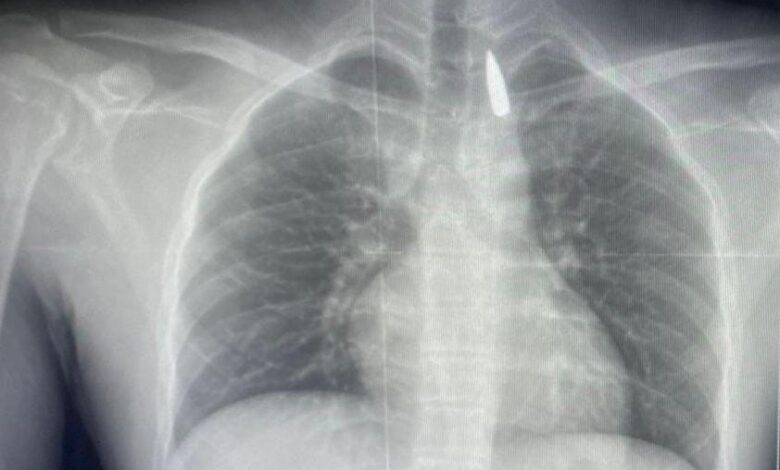

وأوضح الدكتور تامر عبد الله، عميد كلية الطب ورئيس مجلس إدارة المستشفيات الجامعية، أنه في يوم 21 أكتوبر 2025 تمكن فريق من أطباء قسم جراحة القلب والصدر والتخدير والمعاونين من إجراء جراحة دقيقة بالغة الخطورة لأحد المرضى المحجوزين من قطاع غزة، والذي كان قد تعرض لإصابة بطلق ناري منذ فترة، استقر المقذوف على إثرها داخل تجويف القفص الصدري قرب الشريان الأورطي، وهو أكبر وأهم شرايين الجسم والمسؤول عن تغذية جميع الأعضاء الحيوية، وأضاف أن الفريق الطبي، رغم دقة الحالة وتعقيدها، نجح في استخراج المقذوف بأمان بعد عملية جراحية نادرة استمرت عدة ساعات داخل المستشفى الجامعي الجديد، حيث خضع المريض بعدها للرعاية الطبية اللازمة، وحالته حاليًا مستقرة وتحت المتابعة الدقيقة من الفريق المختص.